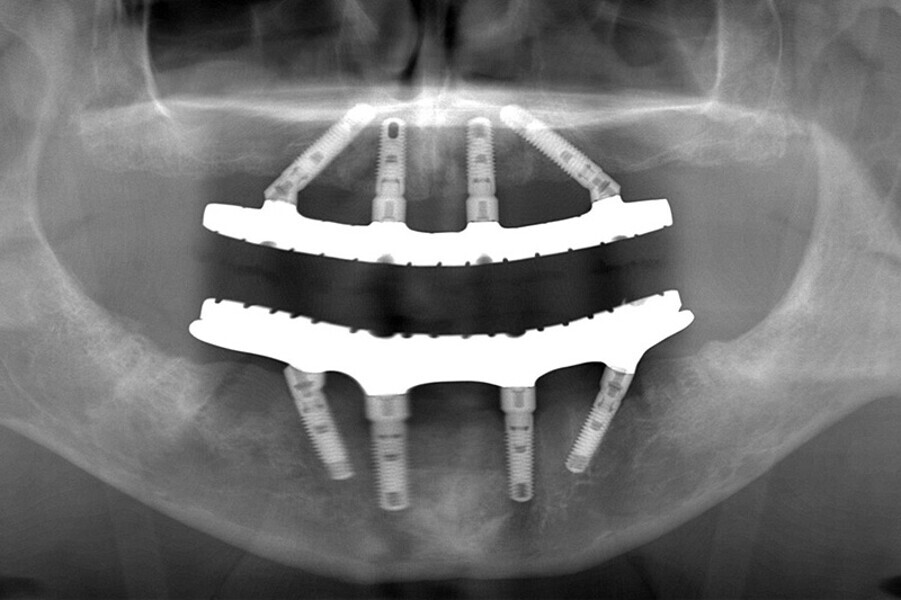

Fig. 7. Rx Pre-operatoria, Prótesis híbrida inmediata con 10 años de evolución y Rx Control a los 10 años.

Fig. 8. Rx Pre-operatoria, Prótesis híbrida inmediata con 10 años de evolución y Rx Control a los 10 años.

Fig. 9. Rx Pre-operatoria, Prótesis híbrida inmediata con 10 años de evolución y Rx Control a los 10 años.

Fig. 10. Prótesis híbrida inmediata con 10 años de evolución y Rx Control a los 10 años.

Fig. 11. Prótesis híbrida inmediata con 10 años de evolución y Rx Control a los 10 años.